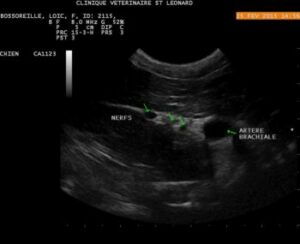

L’animal est en décubitus latéral (ou dorsal), la sonde échographique est placée sur les muscles (superficiel et profond) pectoraux. La première côte et l’artère brachiale servent de référence pour identifier le plexus : les nerfs apparaissent les uns derrière les autres (dans une orientation cranio-caudale), comme des structures rondes hypoéchoiques, entourées d’un tissu hyperéchoique (graisse)

Images échographiques chez le chien (crédit Stephan Mahler) :